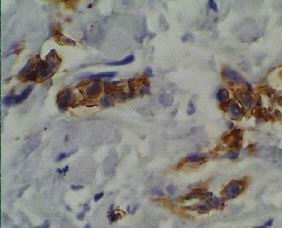

LCIS/LIC consistently E-c negative

false positivity usually in an abnormal

cytoplasmic staining o n l y

DCIS/DIC consistently E-c positive

distinctive cell membrane staining

including Paget disease

(intensity „sometimes“ varying

with high grade DCIS)